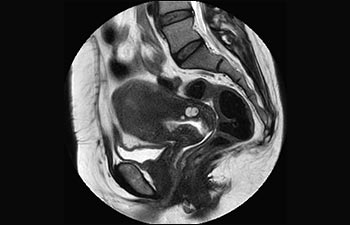

Find the right clinical applications for your needs

See all Ingenia Prodiva 1.5T coils